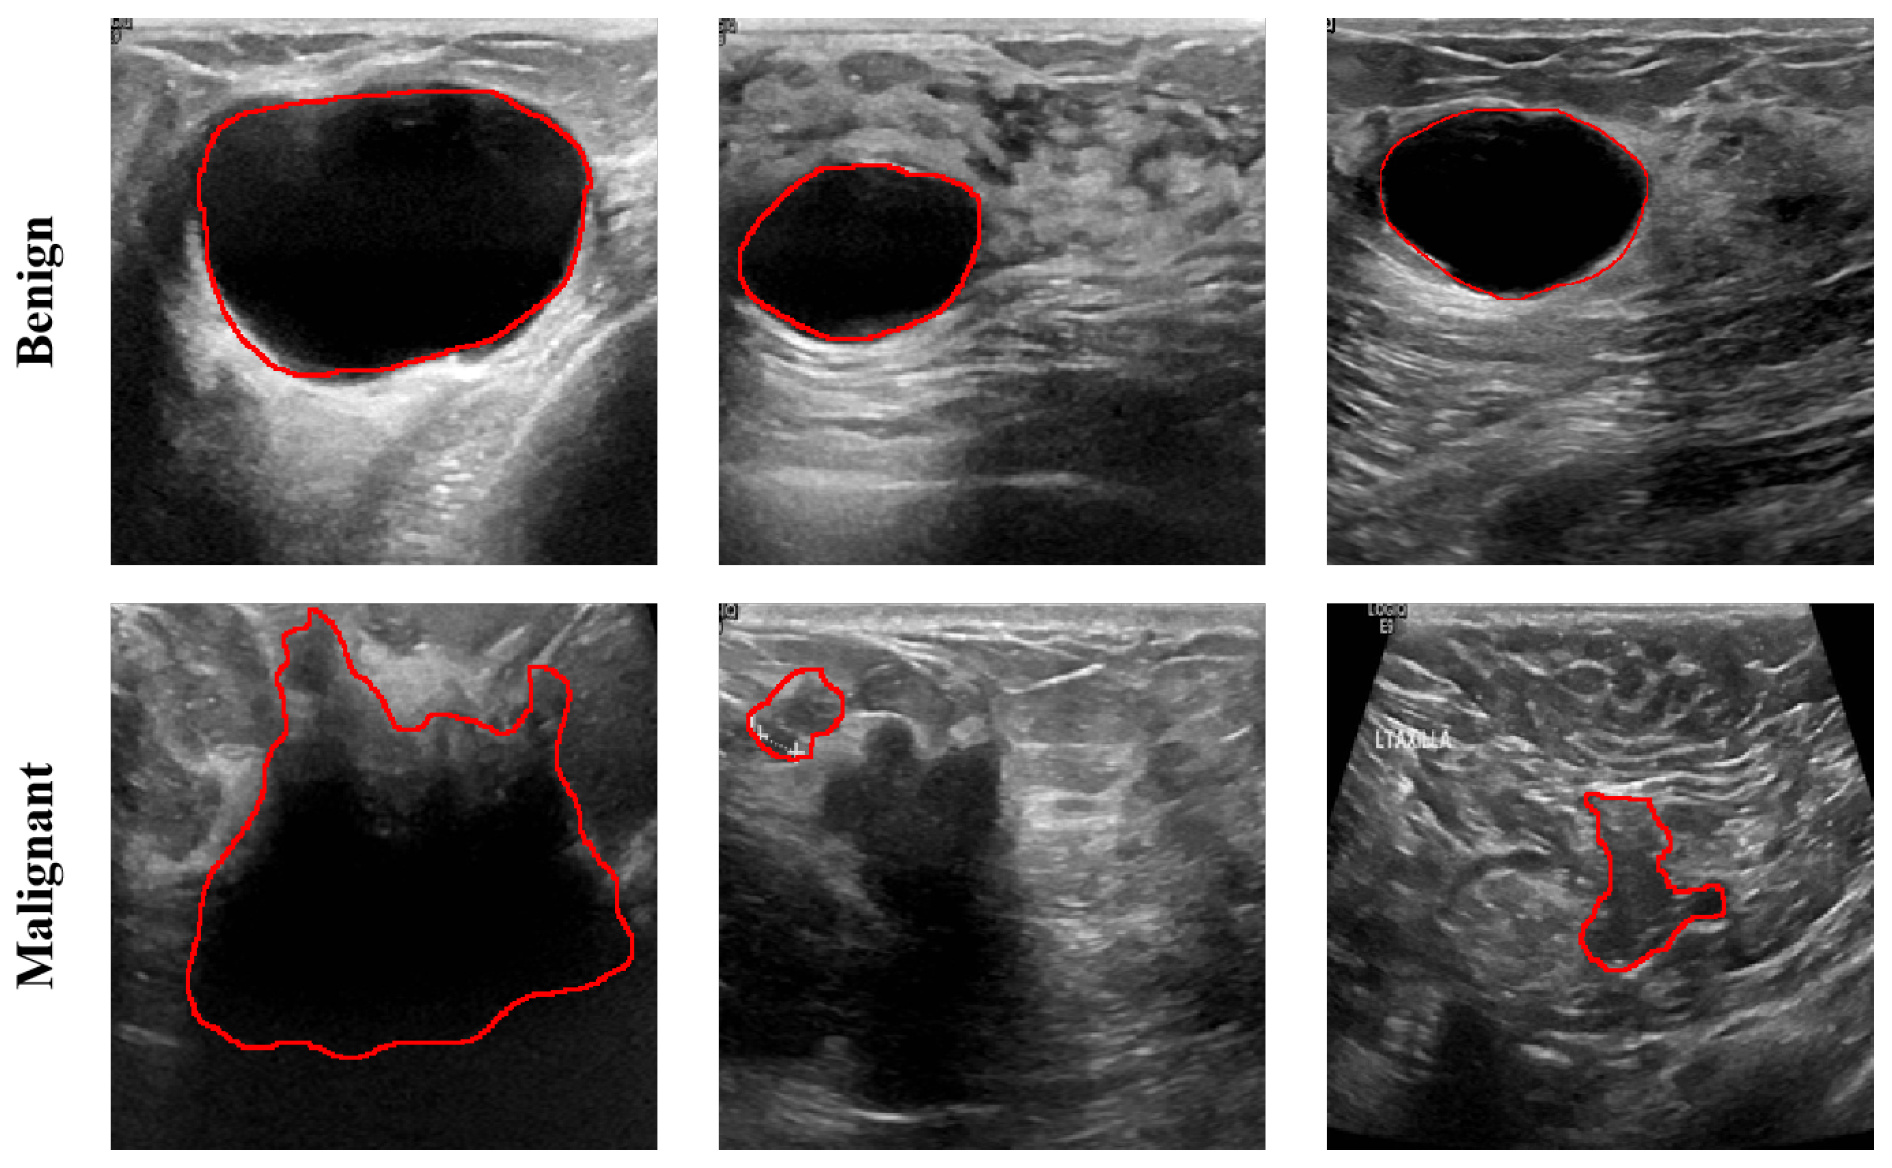

2.1. Dataset Description